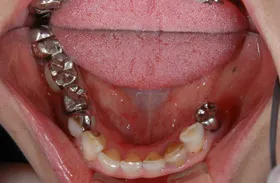

■治療前:生まれつき下顎左右前歯がなく隙間がある

■治療後:矯正治療後、下顎左右3番の2本にインプラント治療

| 主訴 | 生まれつき歯がなく隙間があり、審美障害・咀嚼機能障害がある |

| 治療方法 | インプラント治療 + 矯正治療 |

| 治療期間 | インプラント治療 約6ヶ月 |

| 通院回数等 | インプラント治療 約6回 |

| 費用 | 約94万円(税込) |

| リスク・副作用 | 術後の腫れ・痛み |